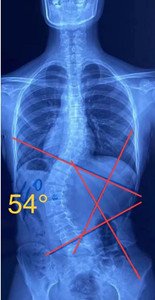

單向側(cè)彎

如果是單向側(cè)彎的患者,(腰彎或者胸彎),躺在床上,應(yīng)向患側(cè)處進(jìn)行臥位,側(cè)臥在你彎弧的凹側(cè),讓它下墜打開。

針對于腰椎單彎,還有另一種側(cè)躺姿勢:比如存在腰椎的左側(cè)彎,凸側(cè)在下

,在頂椎下加一個圓形壓墊(將毛巾卷成圓柱體,直徑約5-10公分),使其把相反凹側(cè)方向的脊柱給頂起。(頂起后從背后觀察,用手去觸摸到脊柱在中線上,成為一條直線,說明動作正確。如果頂起程度能達(dá)到過矯的效果,為最佳)。

S型側(cè)彎,無論向哪個方向側(cè)躺,對其中一邊的彎度都是不利的,這種情況盡量以平躺為主。